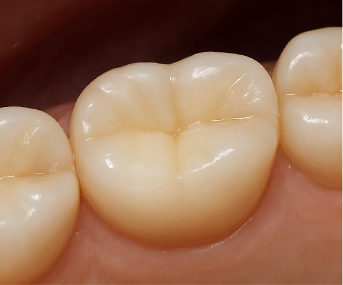

Why Do Many People Choose Zirconia Crowns?

Zirconia is a material that has

a color similar to natural teeth

and strong durability at the same time.

In visible areas like the front teeth,

the color should not look dark or metallic,

and in high-pressure areas like the molars,

the material needs to remain strong for a long time.

Because zirconia satisfies these two points

in a relatively balanced way,

it is a crown material that is widely chosen

for both front teeth and molars.